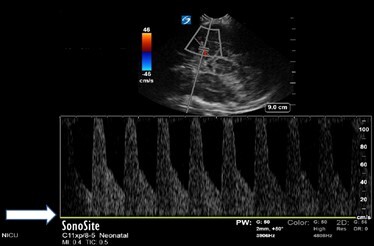

Neonatology Normal Anatomy No Aliasing Image